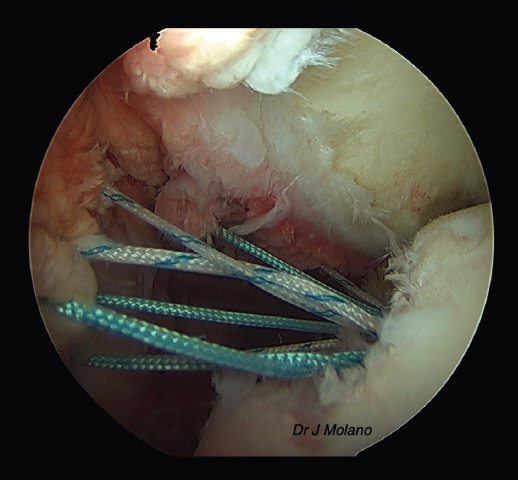

Posteriormente, se realiza el remplissage por vía artroscópica. Se coloca el artroscopio en el portal anterosuperior y se emplean el anterior y el posterior como portales de trabajo. Desde el portal posterior se realiza el curetaje/raspado superficial de la lesión de Hill-Sachs para conseguir una superficie sangrante. Tras ello, se colocan 2 implantes de tipo Iconix® (Stryker, Kalamazoo, MI, USA) (cargados con 2 hilos de sutura cada uno) desde el portal posterior próximos a la parte más medial del defecto de Hill-Sachs. Se recupera cada cabo de sutura de manera independiente a través del tejido capsular/infraespinoso con una pinza grasper, quedando estos en la misma línea mediolateral para ser anudadas sobre el infraespinoso al final del tiempo artroscópico(14) (Figuras 2 y 3).

Figura 2. Visión artroscópica desde el portal superior de un hombro derecho con lesión Hill-Sachs off track; defecto glenoideo del 20%.